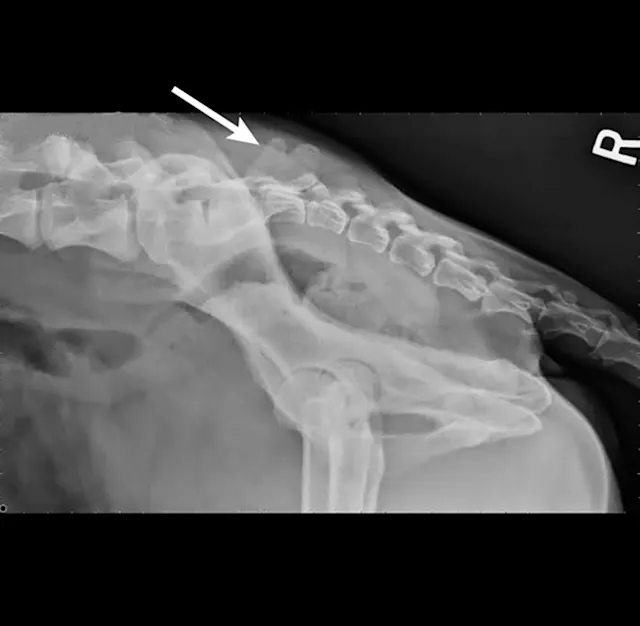

Survey radiography of the lumbar spine, pelvis, and hips is recommended. Common abnormalities identified in patients with LS disease include vertebral spondylosis, sclerosis of the vertebral end plates, and collapsed L7-S1 disk space. Stress radiography may exacerbate a lumbosacral step, which can further aid in diagnosis. Radiographs are also recommended to help rule out metastatic disease, diskospondylitis, trauma, or luxation (Figures 1-3).

Figure 1

Right lateral radiograph of a dog demonstrating L7 fracture. Images courtesy of Dr Tammy Stevenson.